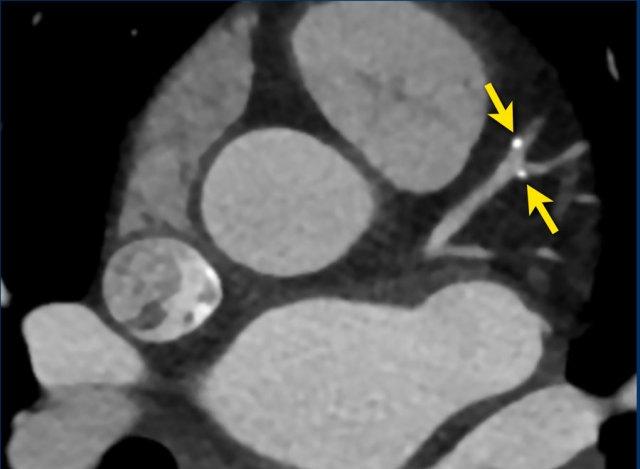

Spotty calcification

Spotty calcifications are usually defined as calcifications < 3

mm.

Small spotty calcifications on CTA are associated with high-risk plaques (12).